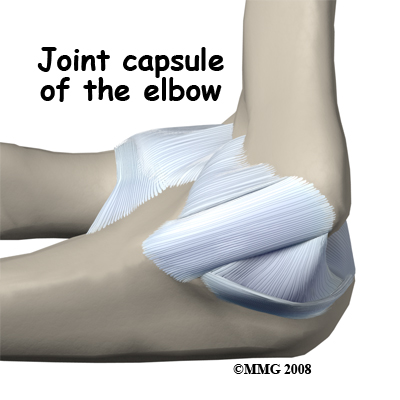

There are several important ligaments in the elbow. Ligaments are soft tissue structures that connect bones to bones. The ligaments around a joint usually combine together to form a joint capsule. A joint capsule is a watertight sac that surrounds a joint and contains lubricating fluid called synovial fluid.

In the elbow, two of the most important ligaments are the ulnar collateral ligament (UCL) and the lateral collateral ligament. The UCL is also known as the medial collateral ligament. The ulnar collateral ligament is on the medial (the side of the elbow that's next to the body) side of the elbow and the lateral collateral is on the outside. The ulnar collateral ligament is a thick band of ligamentous tissue that forms a triangular shape along the medial elbow. It has an anterior bundle, posterior bundle, and a thinner, transverse ligament.

Together these two ligaments, the ulnar (or medial) collateral and the lateral collateral, connect the humerus to the ulna and keep it tightly in place as it slides through the groove at the end of the humerus. These ligaments are the main source of stability for the elbow. They can be torn when there is an injury or dislocation of the elbow. If they do not heal correctly the elbow can be too loose or unstable. The ulnar collateral ligament can also be damaged by overuse and repetitive stress, such as the throwing motion.